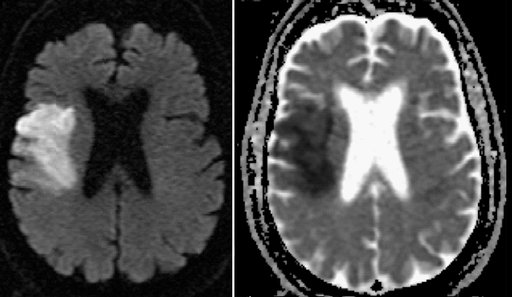

DWI restricted diffusion in left MCA territory, abrupt left M2 cutoff on MRA